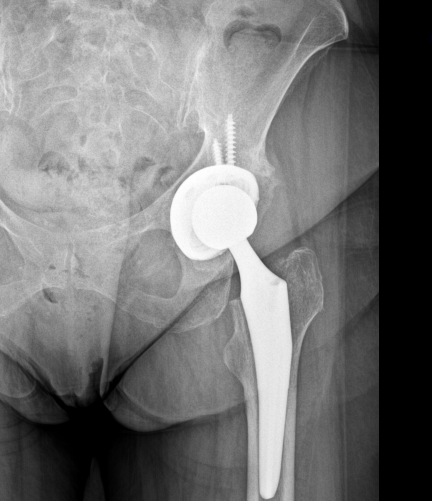

Kalça protezi aşınan ve yıpranan eklemde pelvis  ( leğen ) kemiğine soket tarzı bir metal, femur kemiğine de stem dediğimiz uzun sapı olan bir metal, her 2 metal arasına da polietilen ( hastanın yaşına göre seramik ) bir aparatın yerleştirilmesidir.

Parsiyel kalça protezinde pelvis kemiğine herhangi bir implant yerleştirilmeyip femur kemiğine uygulanan stemin ucuna femur başını taklit eden bir metal küre yerleştirilir.

Total kalça protezinde ise hem pelvis kemiğine hem de femura implant yerleştirilir. Arasına da polietilen ve seramik olmak üzere 2 tip implant yerleştirilir.